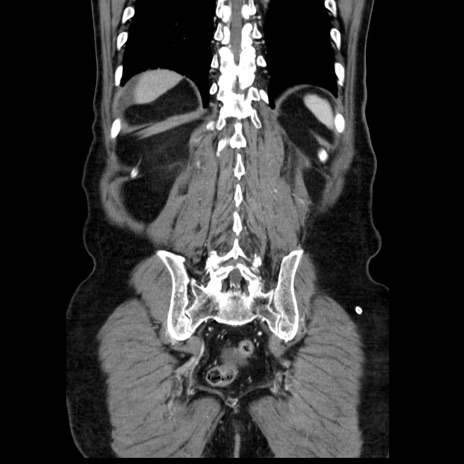

症例30(冠状断像)

【症例】80歳代男性

【主訴】臍周囲痛

【現病歴】約6時間前から臍下部痛が出現。次第に腹部膨隆・背部痛も生じてきたため来院。背部痛の場所は変化しない。

【身体所見】意識清明、BT 36.3℃、BP  131/87mmHg、P 87bpm、SpO2 100%(RA)、臍周囲自発痛・圧痛あり、反跳痛なし、自発痛部位に一致して板状硬あり、腹部膨隆、腸雑音減弱、CVA tenderness両側陰性。

【データ】WBC 19600、CRP 0.33